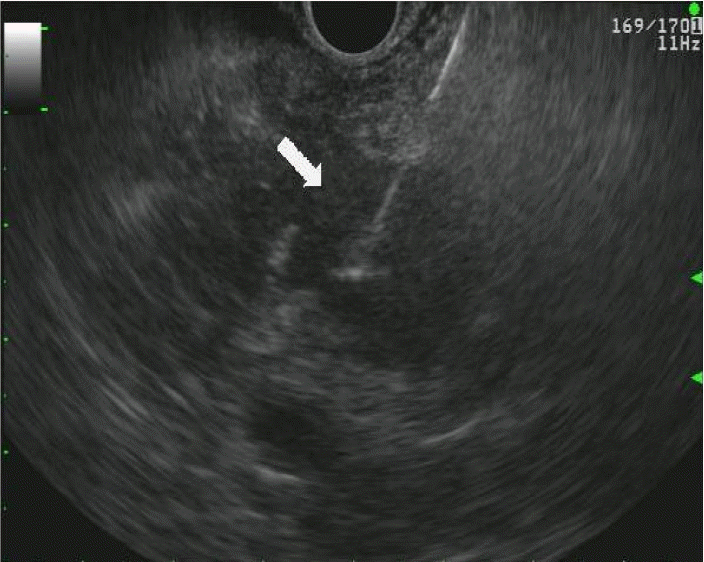

Figure 4.

In the second case, on HD 1, EUS-guided fine-needle aspiration was performed on the low-echoic lesion in the pancreatic neck.